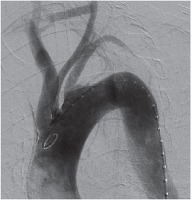

Acute type B aortic dissections can be treated medically, surgically as well as by thoracic endovascular stents (TEVAR). However, presentations and pathology can vary and an isolated strategy may not be adequate in managing the condition satisfactorily. We describe a hybrid approach using surgery and endovascular stents to adequately manage type B dissection in a 76-year-old man, a known hypertensive and chronic smoker who presented to the emergency department with acute retrosternal pain radiating to the neck and back. The patient had intractable pain and refractory hypertension despite optimal medical therapy. Echocardiography showed a large subclavian atheromatous flap. Computed tomography (CT) scan confirmed type B aortic dissection (Fig. 1). In view of the patient being elderly, hypertensive and a chronic heavy smoker, surgical repair was considered to be associated with high risk. As the pathology extended up to the left subclavian artery, endovascular stent placement with a sufficient landing zone would have required occlusion of the left carotid artery. A decision was therefore taken to perform a carotico-carotid bypass and an endovascular stent to treat the type B aortic dissection.